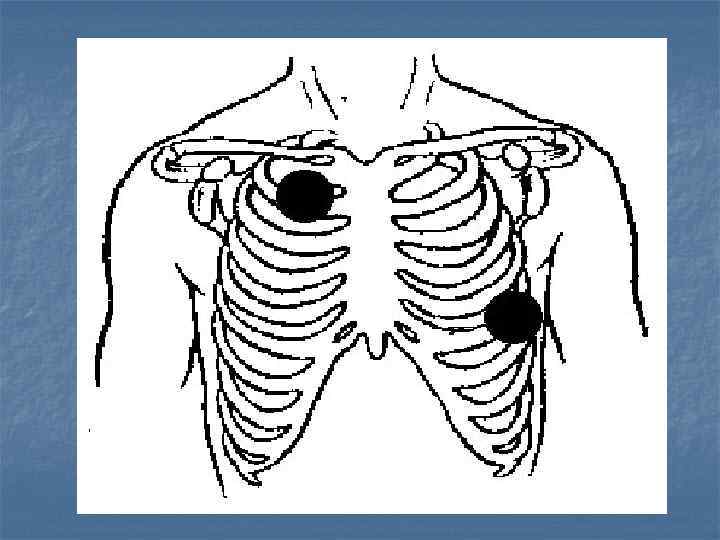

F. Дефибрилляция

Дефибрилляция w w Энергия разрядов (200 Дж – 300 Дж - 360 Дж) Серия из 3 разрядов должна быть проведена менее чем за 1 минуту w Не следует останавливаться между разрядами на СЛР w После проведения разряда оценивайте каротидный пульс NB! Если сразу после разряда на ЭКГ регистрируется асистолия, не следует вводить адреналин/атропин! Необходимо проведение СЛР в течение 1 минуты и затем оценка ритма и проверка пульса